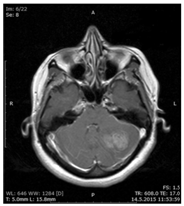

A 28 year-old female patient with long-lasting intermittent nausea was admitted to our hospital with the complaints of nausea, vomiting, and headache. The neurologic examination was normal with normoactive deep tendon reflexes. Cranial MRI revealed a hydrocephalus due to pressure on the 4th ventricle in the left cerebellum (Figure 1) and external ventricular drainage system was applied to the patient. Subsequent contrast-enhanced cranial MRI examination revealed, a massive heterogeneous contrast enhanced lesion which was iso-hypointense in T1 and iso-hyperintense in T2 imagings and located on the lateral left cerebellum and extended to the cerebellopontin angulus, showing compression to the 4th ventricular and extraaxial placement (Figure 2-4). The patient was operated, and the tumor in pink-gray colored, soft and flexible consistency was totally removed. She was followed by external ventricular drainage and the external drainage system was withdrawn with the normalization of Cerebrospinal Fluid(CSF) circulation. The postoperative course was uneventful and she was taken to the chemotherapy and radiotherapy program. At one month control no neurologic sequellea was observed.

Figure 1 Cranial MRI revealed a hydrocephalus due to pressure on the 4th ventricle in the left cerebellum.